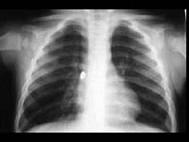

一患儿误吸入一异物,出现呼吸困难,胸部X线片如图,可诊断为 ( )A、肺炎B、以上都不是C、左支气管异物D、右支气管异物E、总支气管异物

问题 一患儿误吸入一异物,出现呼吸困难,胸部X线片如图,可诊断为 ( )

选项 A、肺炎 B、以上都不是 C、左支气管异物 D、右支气管异物 E、总支气管异物

答案 D